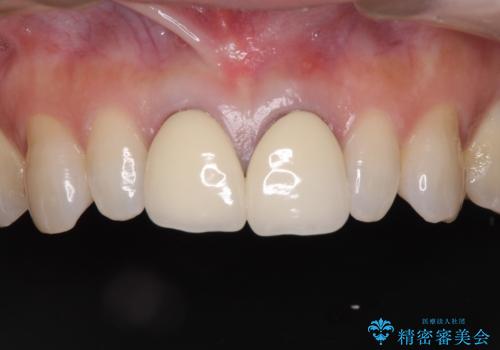

セラミック治療と根管治療を行いました。

金属を使用したメタルボンドクラウンが入っていたため、いつかオールセラミックにしたいときに根管治療も行ったほうが良いとご提案し、今回行いました。

色について

歯と歯肉の境目の色は、歯自体が黒くなっている場合、完全にカバーすることは難しいです。

当院では、清潔な治療を徹底し、顕微鏡を使用した精密な治療を行っています。